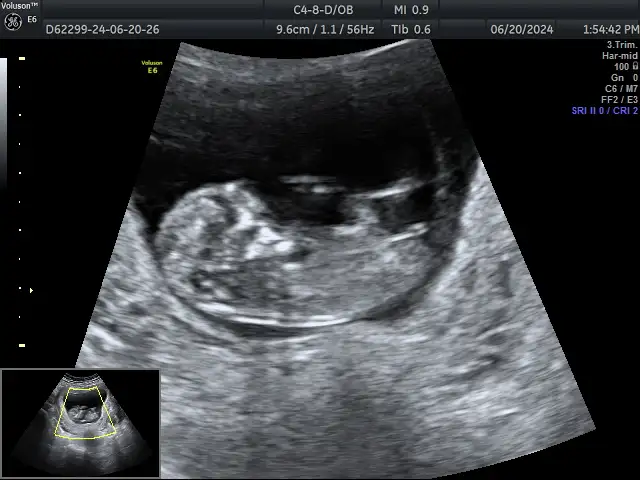

Merhaba kızlar 11+5 cinsytmz kız çok şükür herşey iimis tarama testini verdik. Bizim kız herşeyi gostrdi🤭

Maşallah 🩵özele mi gidiyorsun kuzum .çünkü devlet bu haftalarda söylemiyor da.